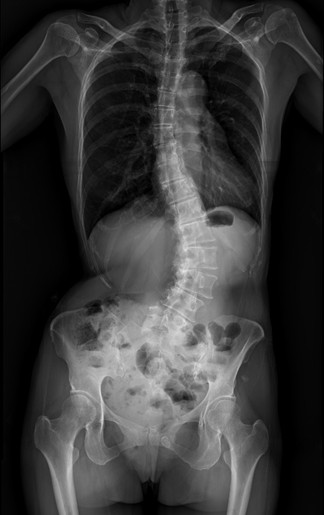

55歲的黃小姐,年輕時曾被健檢醫師提醒脊椎側彎,多年來不以為意,直到近兩年伴隨脊椎劇痛、下肢麻痺與腫脹,夜晚經常因疼痛而失眠。症狀仍持續惡化,甚至到舉步維艱而影響生活。經臺中市立老人復健綜合醫院評估,並接受3D導航微創矯正手術,不但矯正至10度,身高還增加5公分。

張建鈞醫師指出,患者脊椎側彎角度已達48度,屬中重度退化性脊椎側彎,加上合併二尖瓣膜脫垂心臟病史,進行傳統開放式手術風險極高。經完整影像評估與跨科討論後,醫療團隊建議採取微創前開3D導航矯正手術,在不大幅破壞背部肌群的情況下,從側邊小切口進行矯正與支撐重建。手術後恢復快速,術後4至5天即順利出院,疼痛明顯減輕。

共同執行手術的骨科部副部長林琮凱說明,脊椎側彎是指脊椎向側面異常彎曲,並伴隨椎體旋轉變形,並非單純姿勢不良。醫學上以Cobb角度作為判斷依據,超過10度即可診斷為脊椎側彎。若長期未處理,可能導致慢性疼痛、神經壓迫,甚至影響內臟功能。常見類型包含幼年型、非特異型、退化性、神經肌肉型等,其中退化性脊椎側彎多發生於中老年族群,容易被忽略。